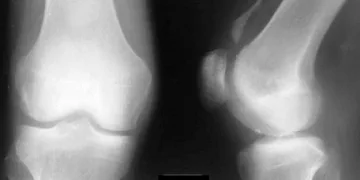

При анализе рентгенограмм коленного сустава важно учитывать, что нормальные структуры и их взаимное расположение имеют ключевое значение для диагностики. На рентгеновских снимках в прямой проекции должен четко прослеживаться суставной зазор, который обычно равномерный и широкий. Нормальные кости, такие как бедренная и большеберцовая, должны иметь гладкие контуры без признаков остеопороза, деформаций или разрушений.

На качественном изображении можно заметить:

• бугорки в области берцовой кости;

• симметрию боковых мышечных блоков;

•轮чертания, обозначающие надколенник;

• частичное открытие головки малой берцовой кости;

• бедренные соединения выше колена;

На рентгенogramme четко видна щель, расположенная между суставными поверхностями. Эта щель представляет собой полупрозрачную линию, в которой находятся хрящ и соединительная ткань.

Внутренние и внешние очертания суставной щели различаются кривизной, если их исследовать под разными углами. На изображении они не выглядят как ровные и непрерывные линии.

Размер нормального пространства в латеральном мениске не должен превышать 8 мм и не быть меньше 6 мм. В медиальном мениске просвет колеблется в пределах от 4 до 6 мм.